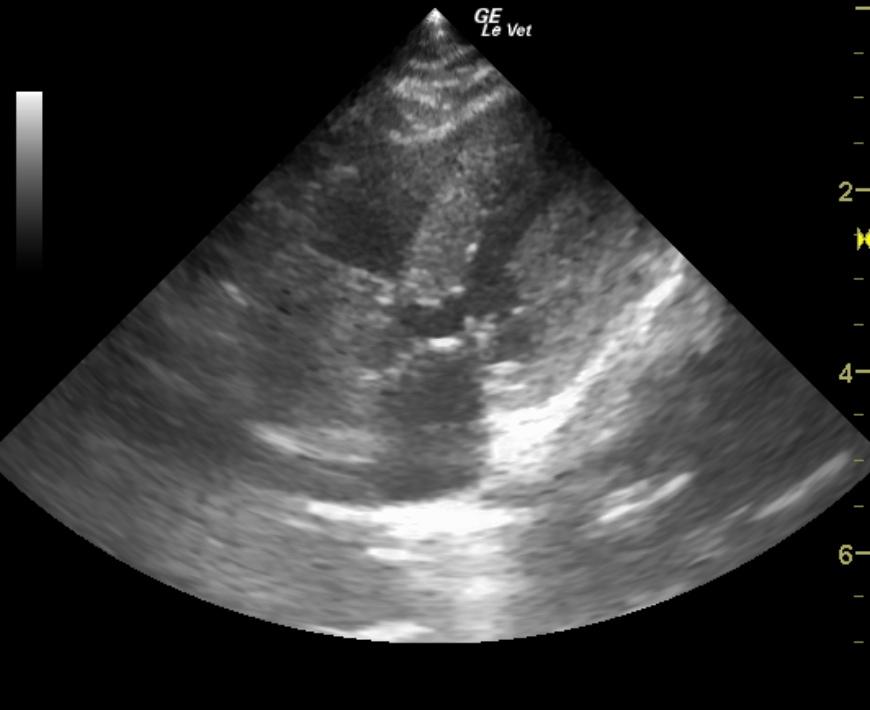

An 11-year-old MN DSH cat presented for sudden onset of hind limb paralysis. CBC and blood chemistry were both within normal limits. Blood pressure measurements were within normal range. MRI revealed lesions suspect for fibrocartilaginous embolism at L6 through the sacrum. Thoracic radiographs showed mild cardiomegaly and a valentine-shaped heart.